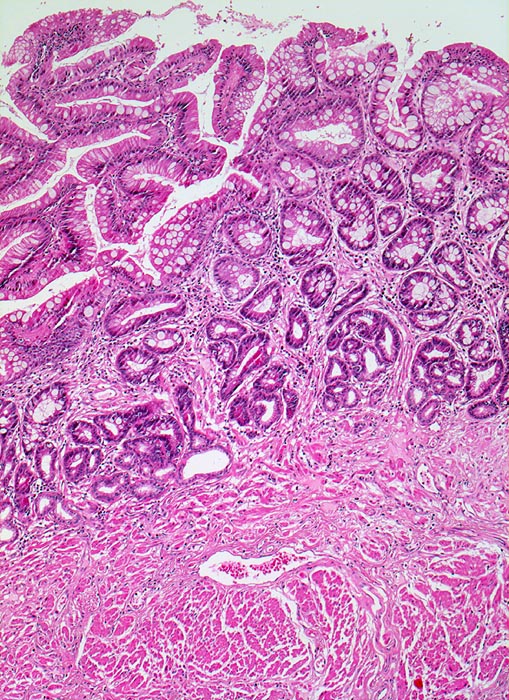

Barrettmukosa

Metaplasie / Heterotopie

Oesophagus, distal

Anstelle von Plattenepithel findet sich eine Zylinderzellmetaplasie mit Becherzellen, welche an Darmschleimhaut erinnert. Das Stroma der Lamina propria ist locker entzündlich infiltriert.

An anderer Stelle im Resektat kann neben schwer dysplastisch veränderter Barrett Mukosa ein Frühstadium eines invasiven Adenokarzinoms nachgewiesen werden.

Seit mehreren Jahren Refluxbeschwerden. In mehrfach wiederholten Untersuchungen wird ein langstreckiger Barrett Ösophagus mit fokaler schwerer Dysplasie nachgewiesen. Es erfolgt die Ösophagektomie.

Der alleinige Nachweis einer Zylinderepithelmetaplasie reicht nicht aus für die Diagnose eines Barrett Ösophagus. Die Bezeichnung Barrett Ösophagus ist Fällen mit Zylinderepithelmetaplasie mit Becherzellen(=spezialisiertes Epithel bzw. intestinale Metaplasie) der Ösophagusschleimhaut vorbehalten. Die Barrettmukosa kann zusätzlich eine leichte oder schwere Dysplasie aufweisen verbunden mit einem erhöhten Risiko für die Entwicklung eines Adenokarzinoms.